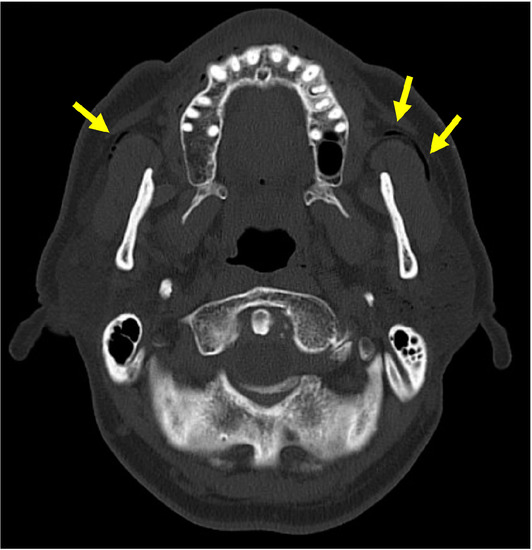

| Diagnostic images, [n (%)] | CT: 95 (55.9%), US: 47 (27.6%), sialography: 35 (20.6%), radiography: 29 (17.1%), sialendoscopy: 13 (7.6%), MRI: 6 (3.5%), fluoroscopy: 1 (0.6%), NR: 26 (15.3%) |

| Imaging findings, [n (%)] | Air in the gland: 100: (58.8%), air in the duct: 55 (32.4%), enlarged duct: 27 (15.9%), emphysema: 19 (11.2%), mass: 14 (8.2%), enlarged gland: 11 (6.5%) |